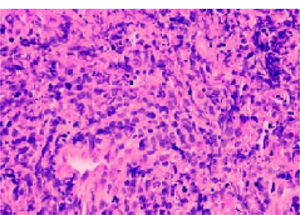

A 45 year old man with a history of IgA nephropathy underwent renal transplant eight years previously. His background history was significant with chronic hepatitis B, on lamivudine and strong family history of hepatocellular carcinoma. His hepatitis B viral DNA was undetectable on treatment. His post transplant course was unremarkable on maintenance regimen of tacrolimus, azathioprine and low dose prednisone until presented with several weeks of high fever 39.5C, low back pain and grossly abnormal liver function test (GGT 862IU/L, ALP 308IU/L, Bilirubin 49 mmol/L (total), 36 mmol/L (direct), AST 137 IU/L, ALT 120 IU/L, LDH 843 IU/L, Alb 25 gm/dL). CT scan of the abdomen revealed multiple hypoattenuating masses extending to the liver surfaces, measuring from 0.2 to 2.0 cm. He also had mild ascites and periportal lymphadenopathy. Initial differentials include hepatitis B associated hepatocellular carcinoma; however there was no evidence of HBV reactivation. MRI suggested impending cord compression as abnormal soft tissue in the anterior epidural space at C5-6 and L5-S1. A transjugular liver biopsy was performed and diagnosed with aggressively behaving, post transplant lymphoproliferative disease (Diffuse large B-cell lymphomaimage) (Figures 1 and 2). He developed auto tumour lysis syndrome and deteriorated rapidly. Treatment attempted with cyclophosphamide, dexamethasone and rituximab. Patient died in ICU on day 10 of treatment from multiorgan failure secondary to septic shock and tumour lysis syndrome.

18-gauge French liver core biopsy at x400 magnification showing a diffuse infiltrate of predominantly large neoplastic lymphoid cells, with strong membrane staining for CD20 indicative of diffuse large B cell lymphoma and, in this context, consistent with monomorphic Post Transplant Lym-phoproliferative Disorder (PTLD).